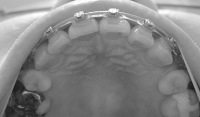

上から。

2008/4/15撮影

2008/5/20撮影

右側の隙間は0.5ミリになりました。

左側は1ミリほどの隙間が2箇所残ってます。